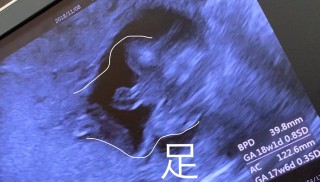

性別わかるかもと期待して来た検診!先生に性別わかりますか?と聞くと、笑いながら面白い格好してて今日はわからないなーと一言。足を揃えて上に上げてる、、なんちゅー格好しとんねんわらわらもー可愛くて仕方ない。初めての赤ちゃんだから性別なんてどっちでもいーけどやっぱり早く知りたかったなー手で抱え込んでる様子みるとまだ教えてくれる気はなさそうな感じかな?親バカかもしれないけど、うちのこ頭の形がいーね!なんてパパと話して、会える日が一段と楽しみになりました♪

BPD=3.90cm

AC=11.69cm

FL=2.48cm

EFW=165g

指が見えてるよと先生に言われました。